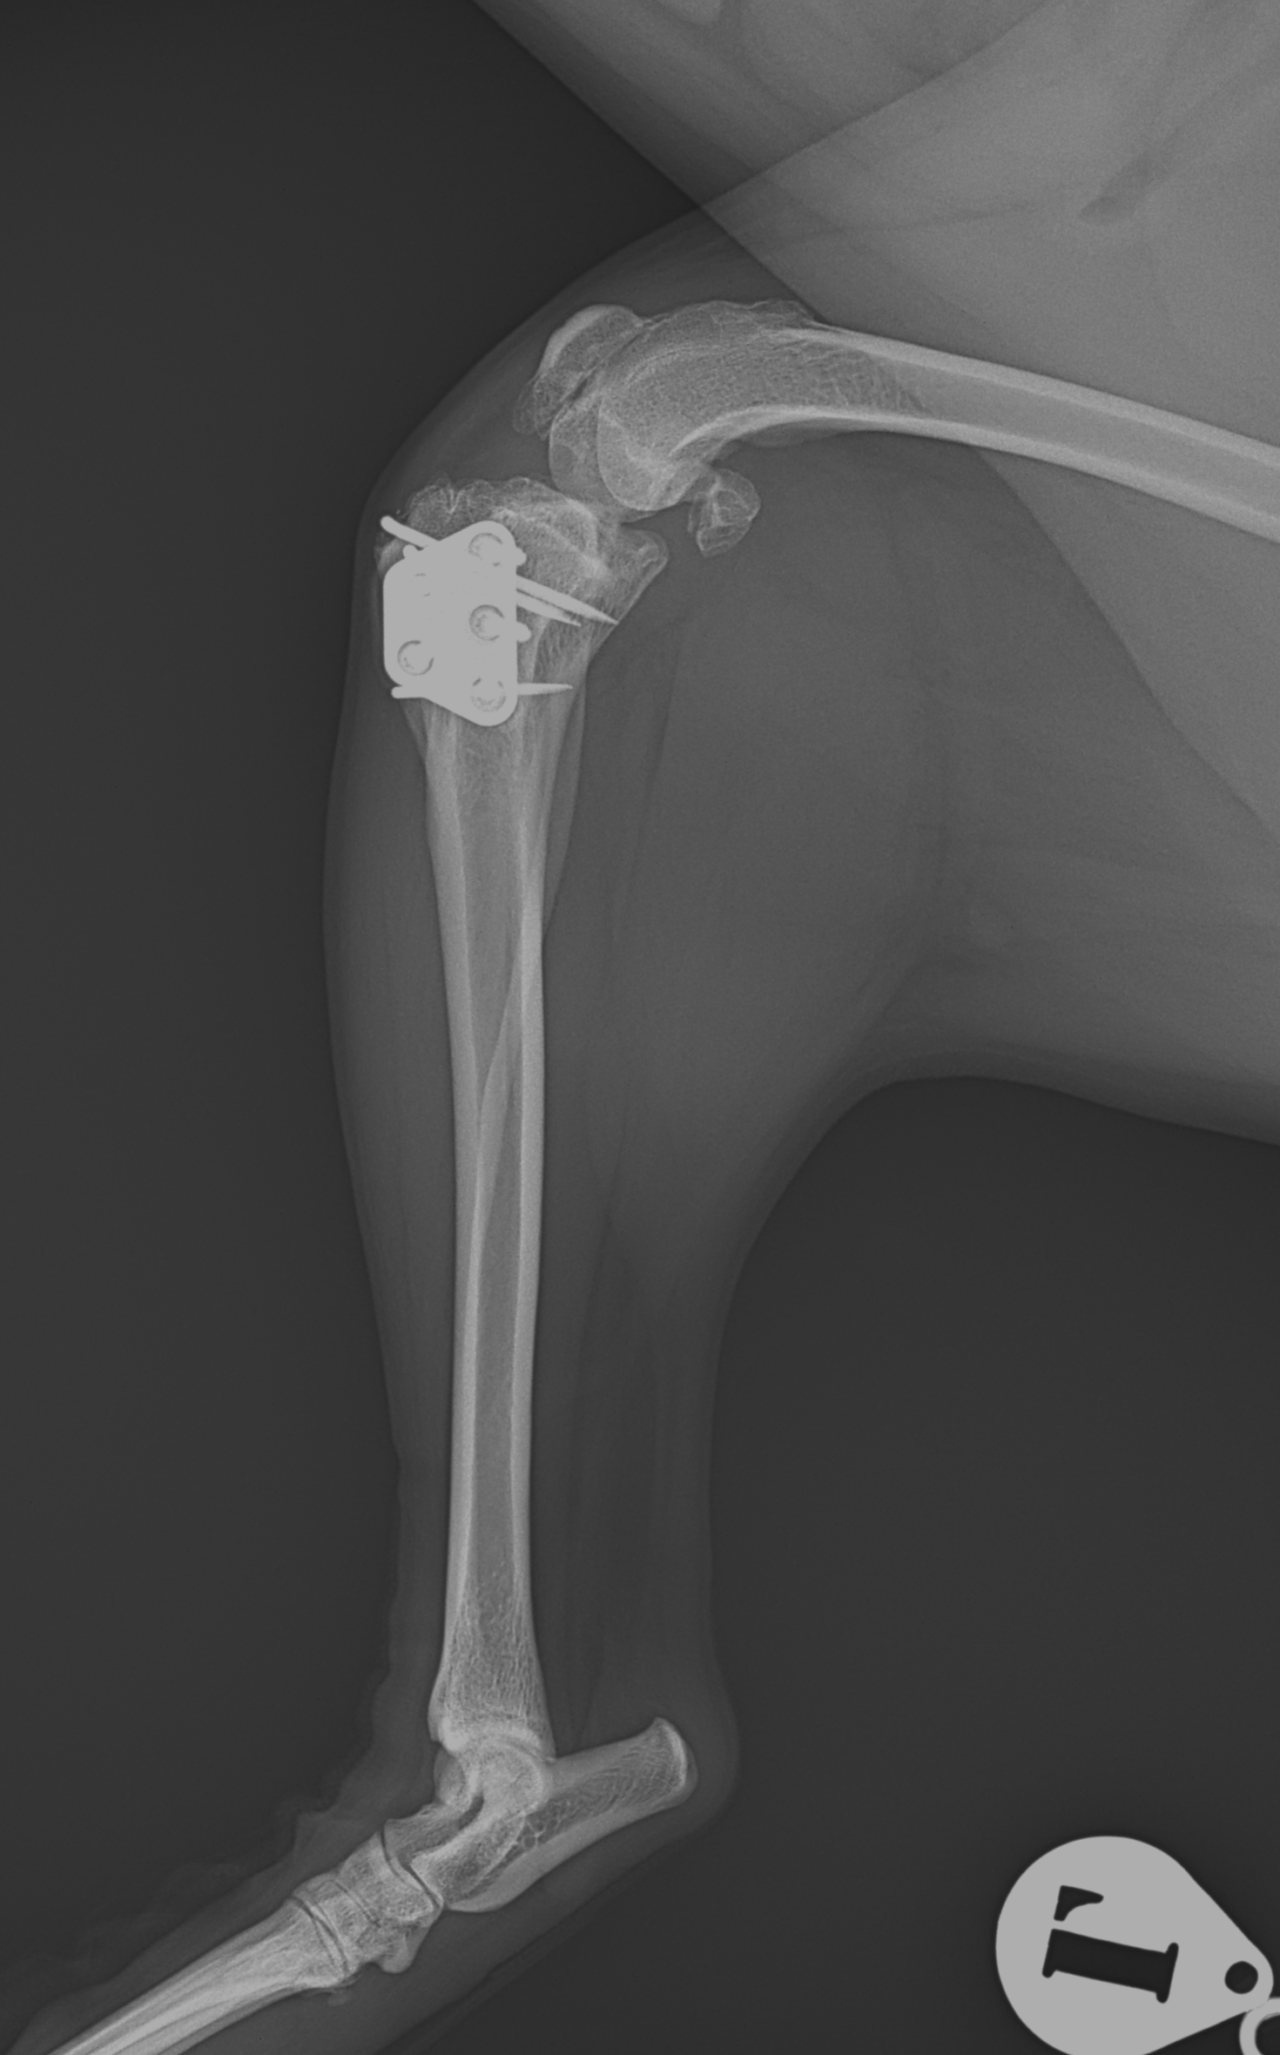

膝蓋骨内方脱臼+前十字靭帯断裂 PGR#21+CBLO #251

過去に膝蓋骨内方脱臼G4で手術を受けている患者さんが、急に跛行を呈するようになったとの事。関節炎が顕著であり、前十字靭帯断裂の併発も疑われます。ファットパッドサイン陽性、脛骨圧迫試験陽性、脛骨ピボット圧迫試験陰性でした。大腿骨滑車のリプレイスメントとCBLOで対応しました。